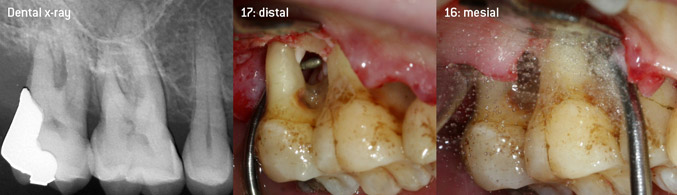

As initiators of the development of the new diamond-coated 3AP air scaler tip, the two dentists recognized the need for improvement of the handling restrictions of the commercially available diamond-coated tips, especially during furcation treatment and when working in tight intraosseous pockets. This should be possible for both non-surgical (Figure 2) and surgical (Figure 3) procedures.

Open debridement of the furcations on teeth 16 and 17

Fig. 3: Open debridement of the furcations on teeth 16 and 17 in case of advanced attachment loss

The aim was to develop a universally applicable tip in order to avoid time-consuming tip changes. In addition, it should be easier to use the new working tips in tight intraosseous pockets from distal and at the distal furcation entrance of maxillary molars, allowing more effective use of instruments as a result. This was achieved by employing an instrument curve with a larger diameter (Figure 1), which is highly advantageous for closed debridement on teeth with advanced attachment loss and involvement of furcation in particular (Figure 4).

Closed debridement of the furcation on tooth 16

Fig. 4: Closed debridement of the furcation on tooth 16 with advanced attachment loss